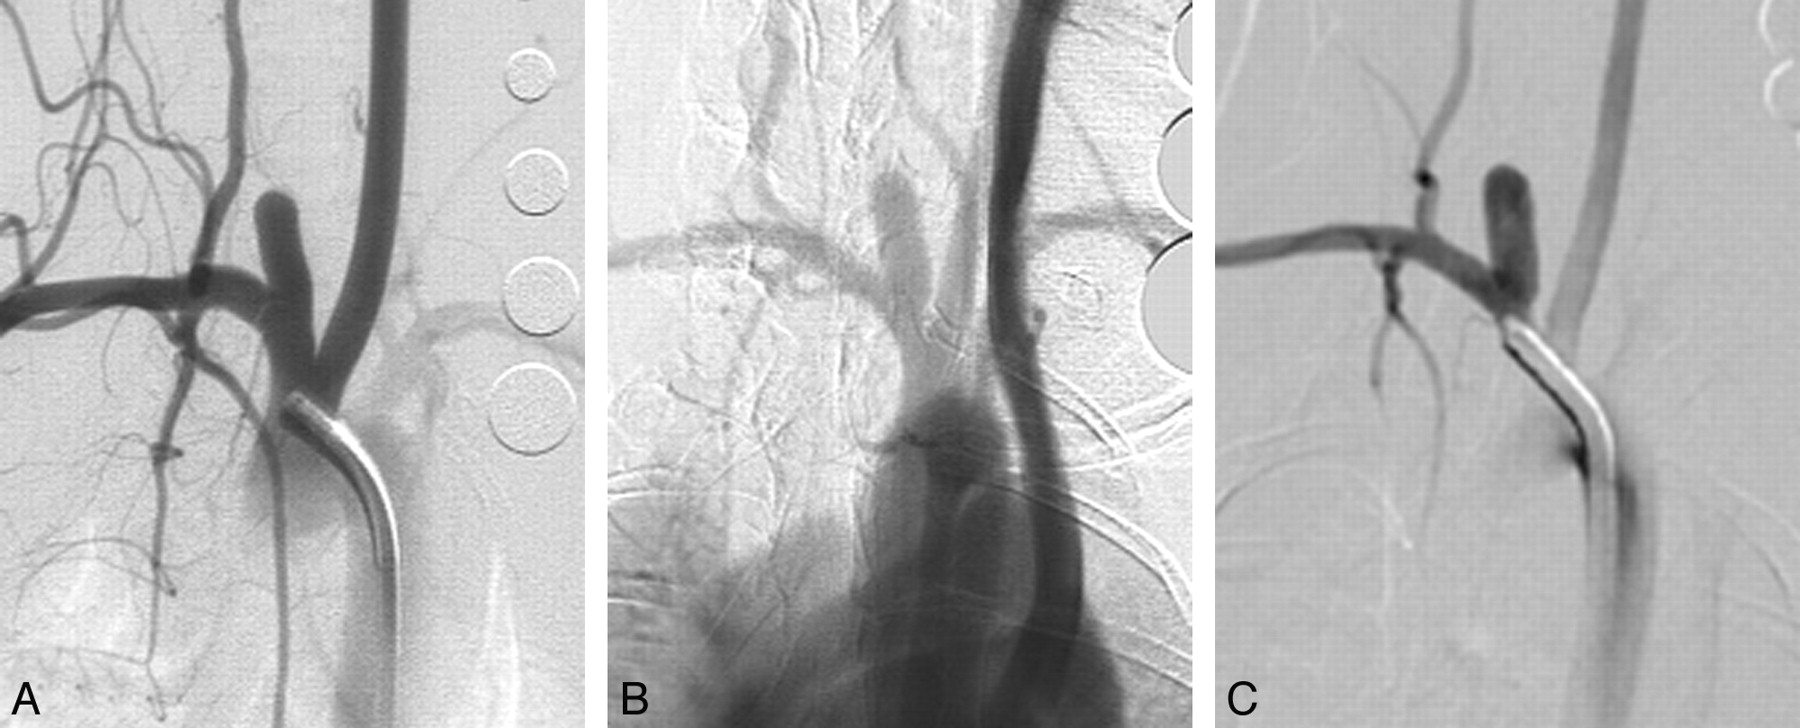

Eleven (11/12, 92%) aneurysms remained completely patent angiographically throughout the 5 years following creation (Figs 1 and 2). At 2 years, a single narrow-neck aneurysm (neck size, 1.4 mm; width, 4:5 mm; ratio of width/neck, 3:2) showed partial thrombosis (Fig 3), which remained stable at 5 years.

Serial DSA in another elastase-induced aneurysm. A, AP IADSA obtained 1 month after creation demonstrates an aneurysm cavity along the brachiocephalic artery, at the origin of the ligated RCCA. B, AP IVDSA in the same aneurysm 2 years after creation. C, AP IADSA in the same aneurysm 5 years after creation. Aneurysm dimensions remain stable throughout follow-up.